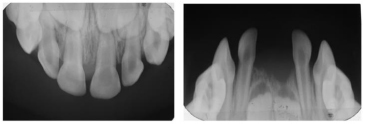

A 3-year-old female patient presented to a dental practice in Lesvos, Greece, in 2015, following the exfoliation of her lower primary central incisors shortly after their eruption. According to her parents, this was initially believed to be self-induced, prompting them to seek dental consultation. Clinical examination revealed intact roots on the exfoliated teeth, no gingival inflammation or bleeding, and no mobility of the other teeth. These findings were consistent with cementum deficiency rather than inflammatory periodontal disease. Anthropometric measurements were within the normal range for age and sex, and family history was negative for premature loss or metabolic disorders. Upper and lower occlusal radiographs were obtained to assess the status of her dentition (Fig. 1). Based on the clinical findings and history, hypophosphatasia (HPP) was suspected, and the child was referred to the hospital for diagnostic workup. Metabolic testing revealed markedly elevated plasma pyridoxal-5′-phosphate (PLP) levels, consistent with tissue-nonspecific alkaline phosphatase deficiency.

Upper and lower occlusal radiographs at age 3, following exfoliation of the mandibular primary central incisors, demonstrating a normal eruption pattern and absence of pathological changes.